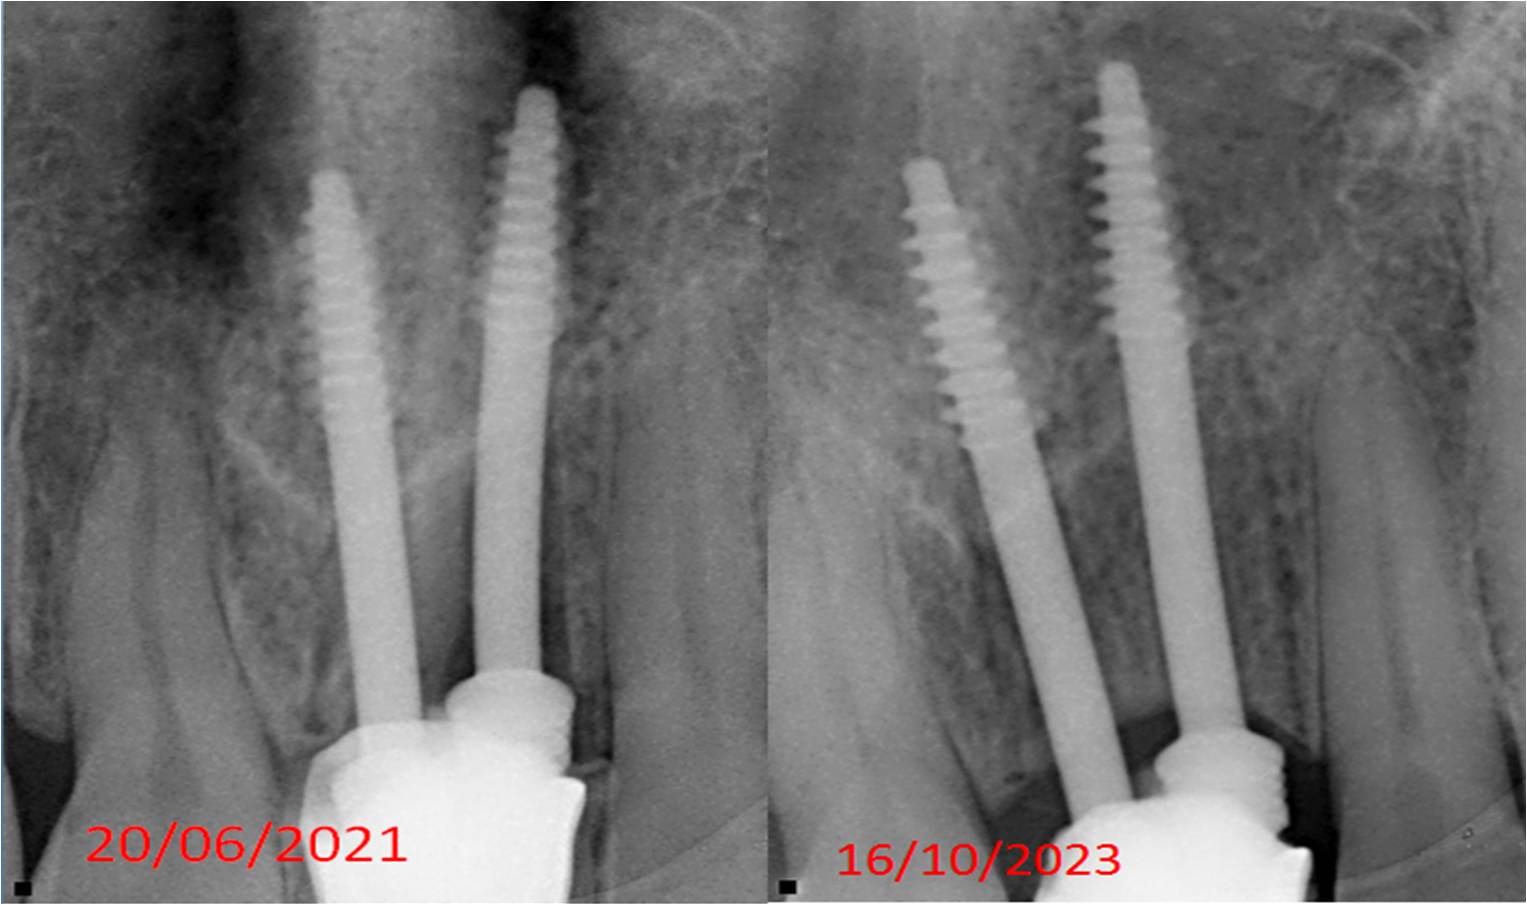

We are a team of 3 certified dentists specialised in offering the best dental treatments in town. With adequate experience of over 17 years, we have mastered the skills of offering the best solutions with the latest technologies.At Sri Durga Specialty Dental Clinic, we are dedicated to providing top-quality dental care in a comfortable and friendly environment. Our team of experienced dentists and staff use the latest technology and techniques to ensure the best outcomes for our patients. From routine check-ups to advanced dental procedures, we offer a comprehensive range of services to meet all your dental needs. We pride ourselves on our patient-centered approach, focusing on personalized care and building lasting relationships.

Cosmetic Dentistry

Root Canals